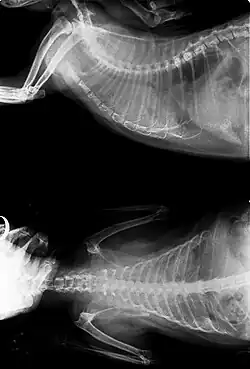

- X-rays may or may not make use of contrast techniques to help visualize the gastrointestinal tract. They are commonly used to identify tumours of the lung, gastrointestinal tract and bladder.